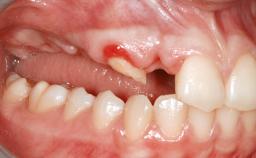

Iliac and Calvarial Bone Blocks for Onlay Grafting of a Severely Resorbed Edentulous Maxilla

A 45-year-old woman with a completely edentulous maxilla was referred to evaluate the possibility of rehabilitation with an implant-supported prosthesis. This patient was healthy and a non-smoker. She had been wearing a maxillary complete denture opposing a natural mandibular dentition since her twenties. This situation had resulted in progressive resorption of the alveolar ridge, repeatedly creating a need for relining the denture. Twenty years later, despite multiple adaptations and the use of “glues” the denture was unstable and causing the patient psychological and functional discomfort.

Bone Augmentation Horizontal|Sinus Floor Elevation|Staged|Vertical

Augmentation Materials Autogenous chips|Autogenous block(s)